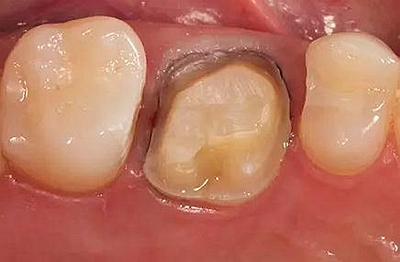

牙體制備完成后的牙合面觀

牙合面觀察牙體預備之后的情況。

軸壁按要求預留0.8 mm 寬度。